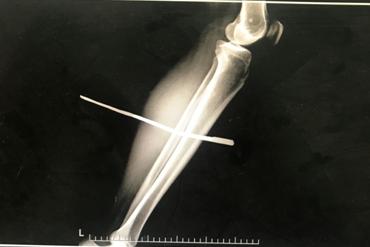

只见他脸色苍白地坐在轮椅上,左腿直直地抬放在轮椅前的凳子上,裤腿高高地挽起,一根长约40公分的铁棍赫然从他的左小腿穿过。

X光检查显示,铁钳从他小腿的胫骨和腓骨之间挨着骨头穿过,虽然没有伤及骨头,但是否会有其他血管、神经的损伤还未知。

而且铁钳锈迹斑斑,感染的机率很高,情况并不乐观,必须马上手术取出铁钳。